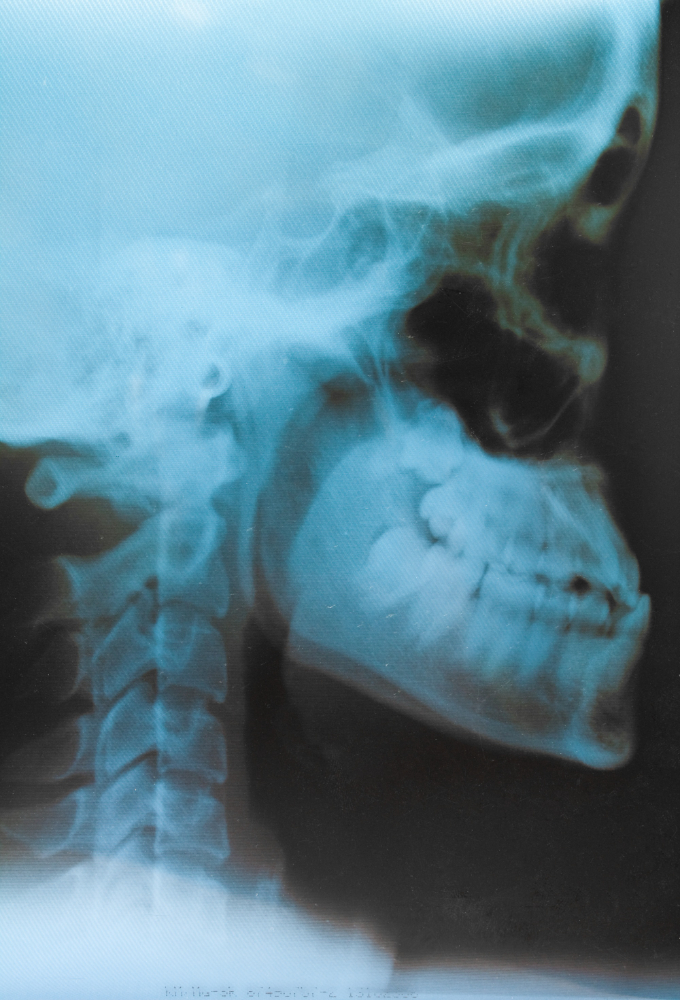

The X-Ray Townes AP View, also known as the Occipital View X-Ray, is a special radiographic technique used to visualize the occipital bone, foramen magnum, and upper cervical spine. This diagnostic test is particularly helpful for evaluating skull base injuries, fractures, and abnormalities around the craniovertebral junction.

The Townes AP X-Ray plays a crucial role in neuro and orthopedic diagnostics. It provides a clear view of the occipital bone and posterior fossa, which are difficult to assess in standard anteroposterior (AP) or lateral skull views. Doctors recommend this test when they suspect:

By offering a precise image of the posterior skull base, the Townes view aids surgeons and neurologists in accurate diagnosis and treatment planning.